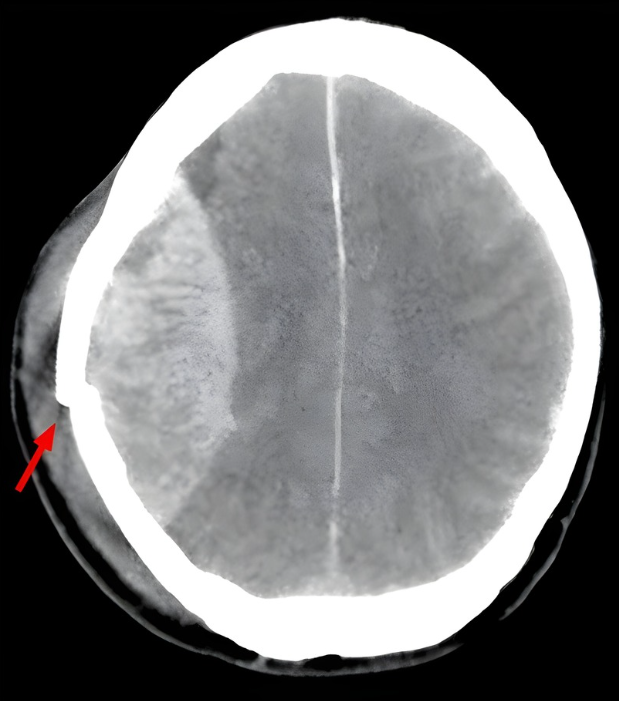

4

Q

what does this CT head show?

A

extradural haematoma

- biconvex lemon shaped hyperdense mass

- bleeding limited by sutures

- midline shift

- associated skull fracture